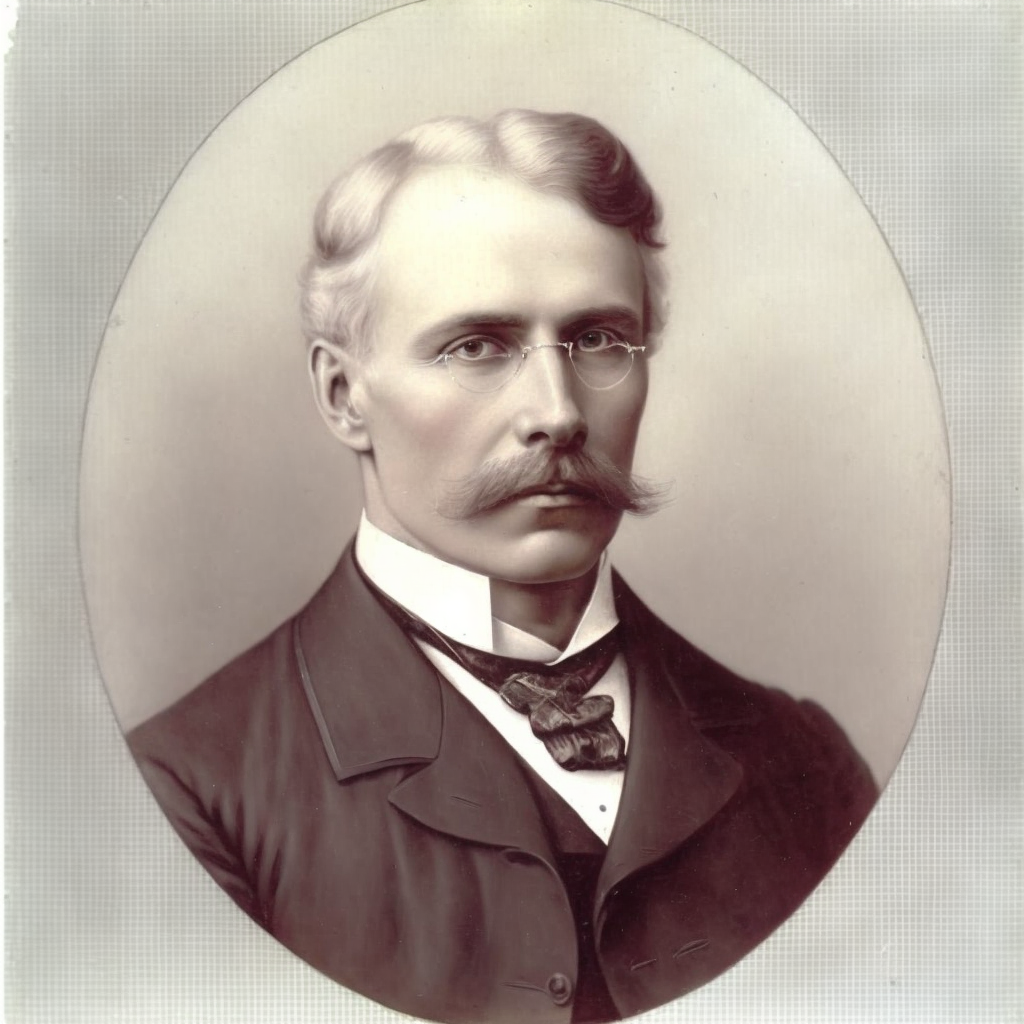

Fransız psikiyatrist Jules Cotard‘dan (1840-1889) tarafından ilk defa tarif edilmiştir. Cotard sendromu, ölü, çürüyen veya var olmayan biri olduğuna dair üzücü sanrısal inançtır. Belirtiler karmaşıktır. Etkilenenler ruhun, kendi bedenlerinin veya… Devamını oku